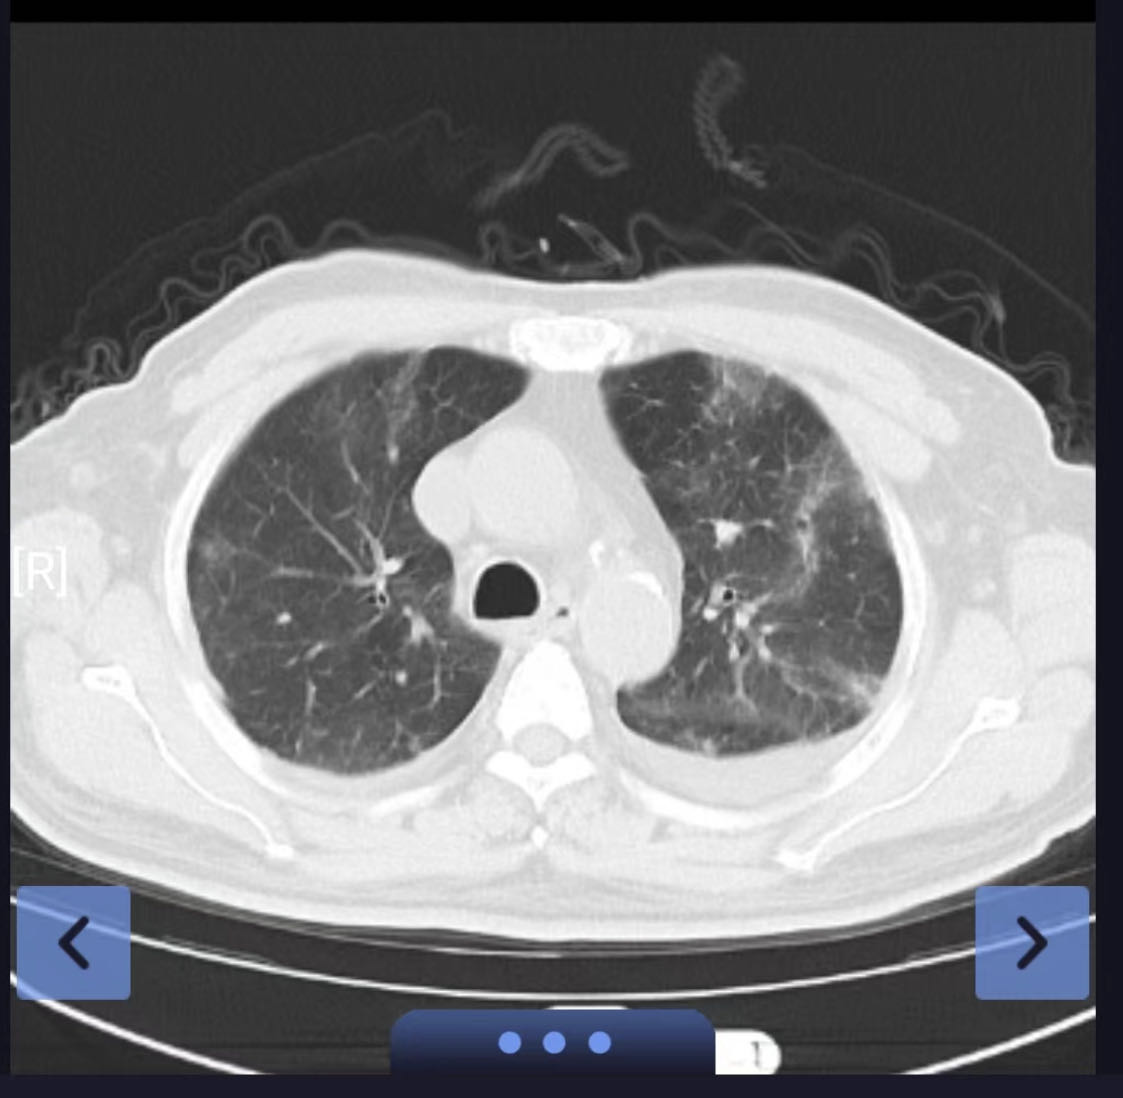

吴某,男,79岁,因发热7天来院就诊,既往有高血压病、糖尿病、冠心病、脑梗塞病史,外院核酸检测阳性,肺部CT提示病毒性肺炎。入院时C-反应蛋白、白介素-6、降钙素原等炎症指标均偏高,入院后给予积极氧疗、抗病毒、抗炎、止咳化痰等对症支持治疗。,患者畏寒发热情况虽有所缓解,但是氧合指数却出现恶化趋势,立即复查肺部CT后显示为“大白肺”。病情急转而下,谢丽华教授立即组织全科医生为该患者进行多学科讨论,调整治疗方案,与家属沟通病情。考虑到患者的年龄,患者对ICU的恐惧心理以及家庭经济情况,采用高流量氧疗+俯卧位通气联合药物治疗,密切关注患者病情变化。

患者虽然氧合差,但好在意识清醒。医护人员多次鼓励疏导,增强其抗击疾病信心,叮嘱其积极进食,增强营养;。高流量吸氧后,患者指脉氧能维持在90%以上,并嘱其每日尽可能长时间俯卧位通气。因患者感染新冠病毒诱发炎症风暴,导致危重型新冠肺炎,及时、准确的诊疗是成功的关键。继续奈玛特韦/利托那韦抗病毒治疗、加大甲泼尼龙治疗剂量,同时考虑到炎症风暴导致DIC、血液高凝,给予低分子肝素抗凝。经过以上综合治疗后,患者症状明显缓解,各项化验指标好转,指脉氧饱和度维持在96%以上,最终在治疗后5天停用高流量氧疗,改为鼻导管吸氧。治疗后第七天复查肺部CT,“大白肺”已得到充分逆转,患者也露出了久违的笑容。

前后肺部CT对照(相隔7天)